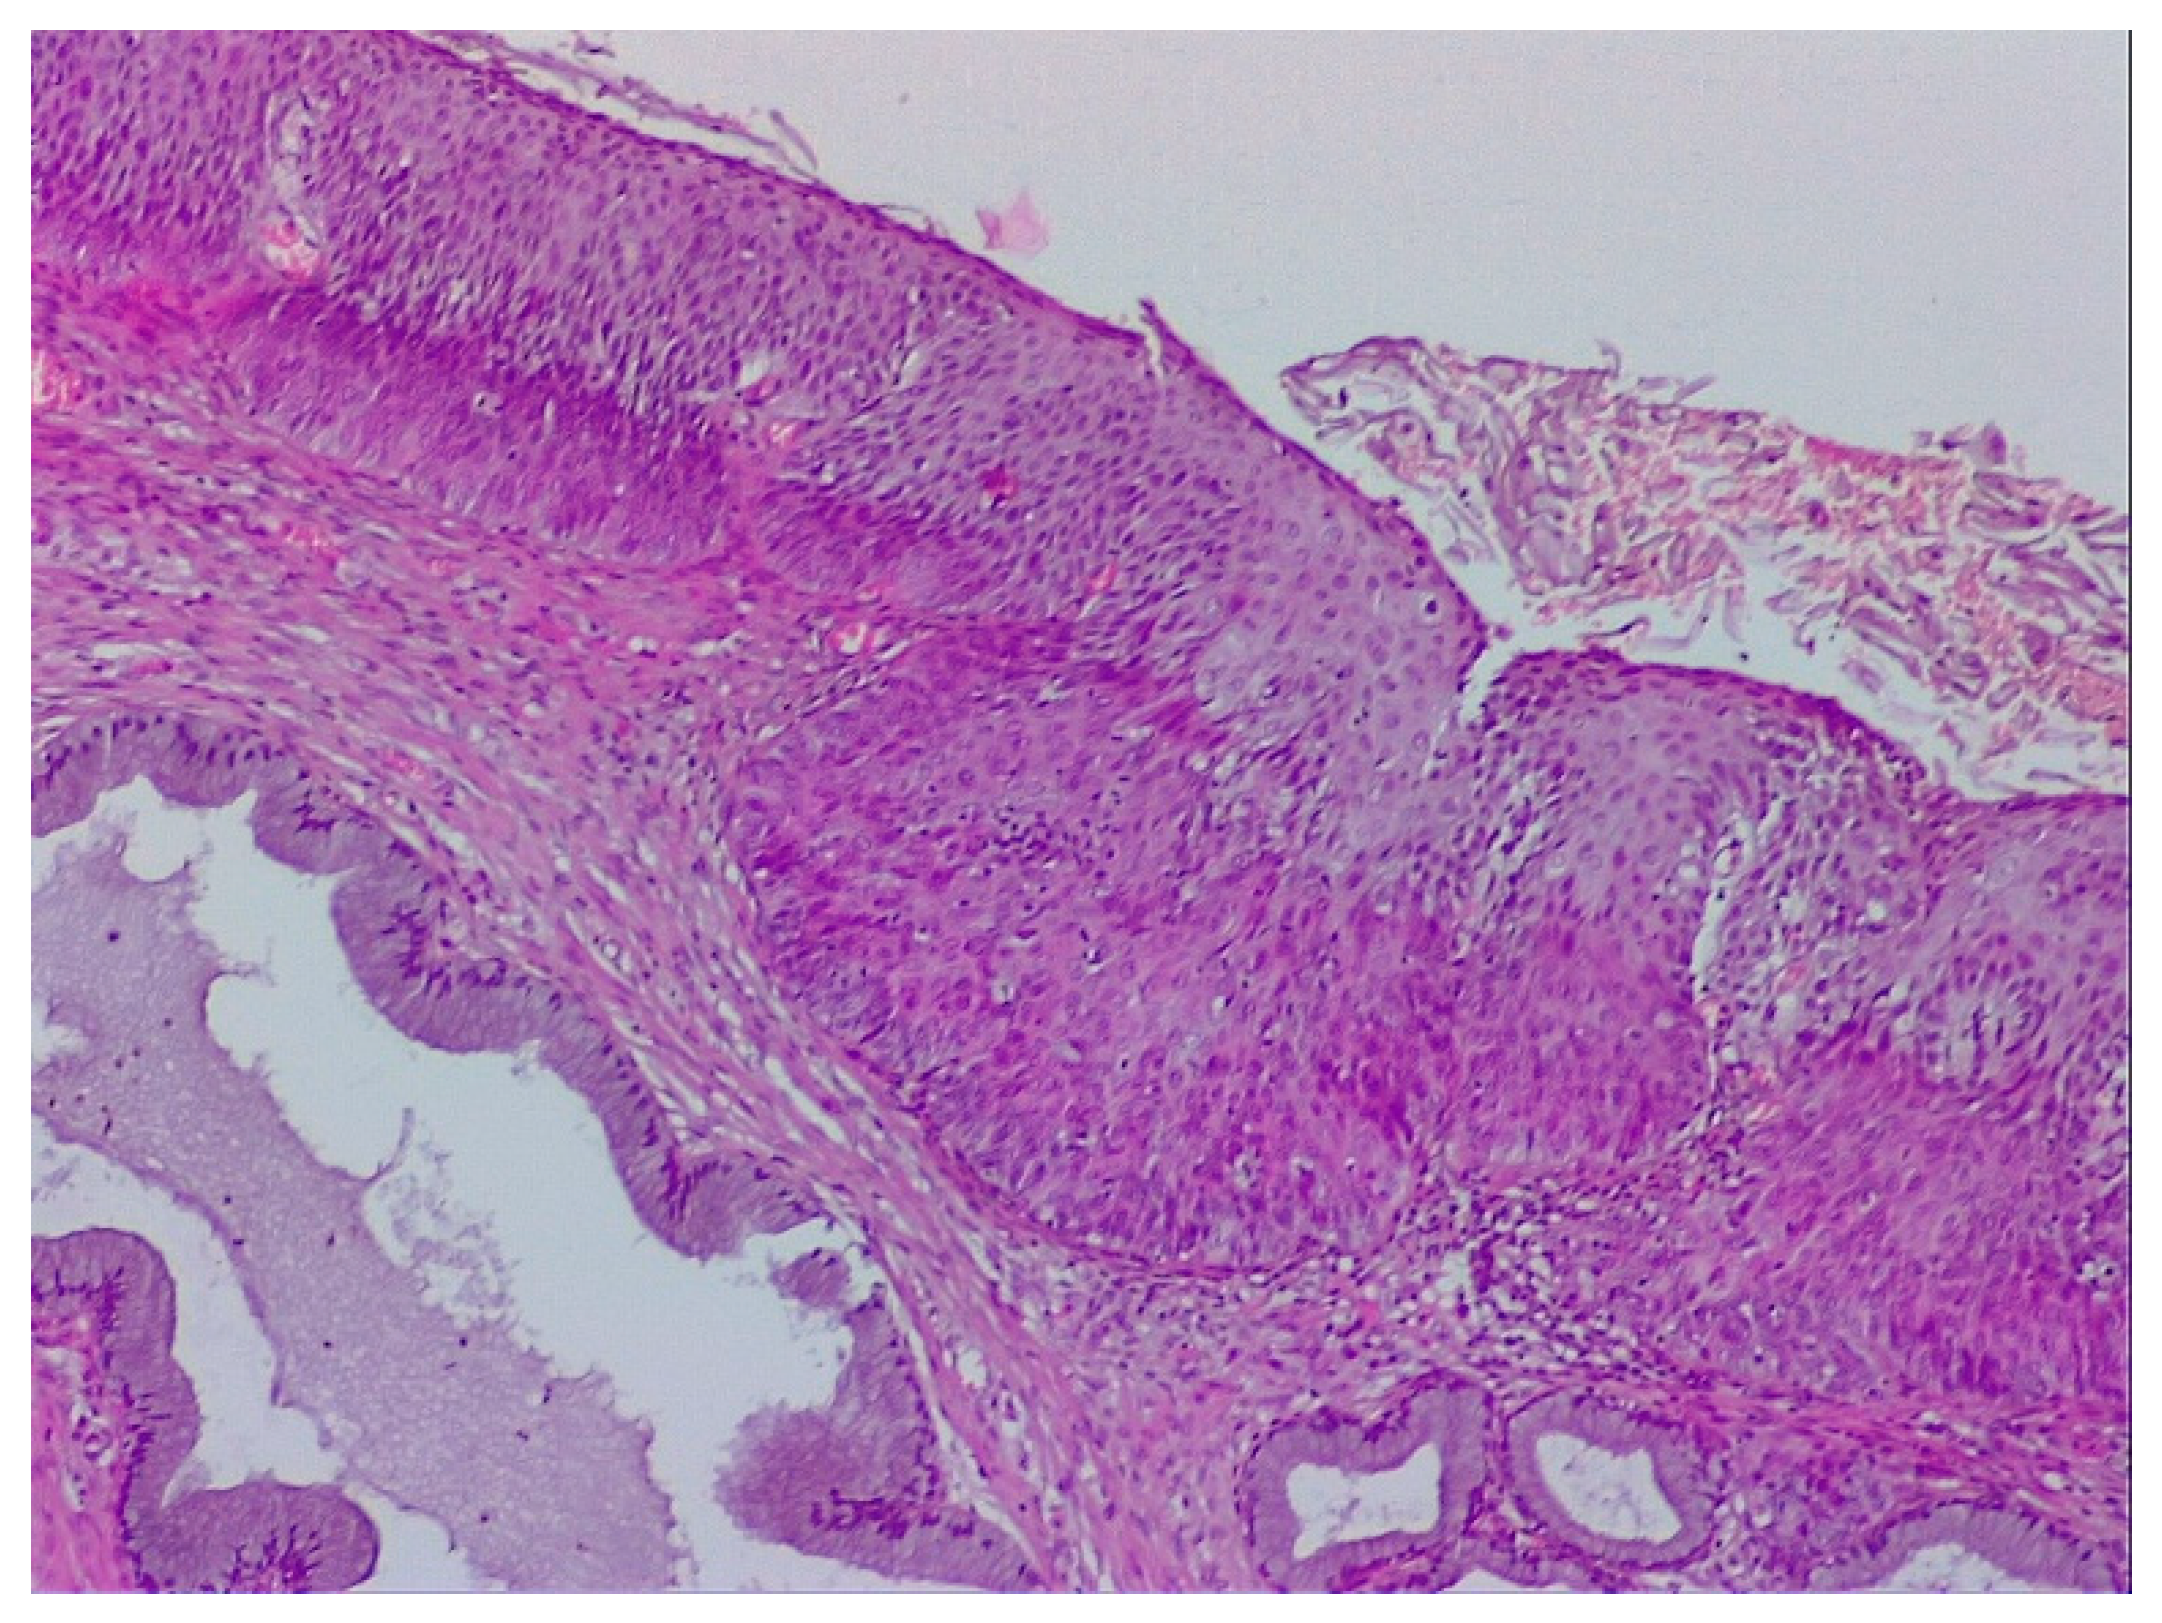

2.2. Clinical Examination